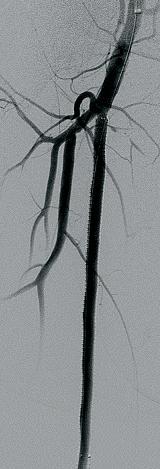

QUESTION FROM MANJ GOHEL, MD, FROM CAMBRIDGE University Hospitals in Cambridge, England, on what the 2023 Charing Cross (CX) International Symposium audience should take back to their multidisciplinary team meetings from the firsttime presentation of BASIL-2 elicited a stark message from chief investigator Andrew Bradbury, MD: a patient who needs a below-theknee revascularization with or without a femoropopliteal revascularization is likely to do better if they are treated with a best endovascular-first strategy rather than a vein bypass-first approach.

In the BASIL-2 (Bypass versus angioplasty for severe ischemia of the leg) trial of 345 patients with chronic limb-threatening ischemia (CLTI), a best endovascular treatment-first revascularization strategy was associated with better amputation-free survival than a vein bypass-first strategy in those who required an infrapopliteal repair—with or without a more proximal infrainguinal procedure. This result was largely driven by fewer deaths in the best endovascular treatment group. Bradbury, from the University of Birmingham in Birmingham, England, presented this key finding during a CX 2023 podium-first presentation. The results were simultaneously published in The Lancet

which could be more endovascular,” Bradbury said in response to Gohel, who was asking a question from the floor of the symposium (April 25–27) taking place in London, England. Alternatively, he added, this could be the point at which the vascular specialist switches over to a bypass approach. BASIL-2, however, “lends quite a lot of weight” to an endovascular-first revascularization strategy, “with all the caveats that we have to consider.”

Bradbury, delivering the data for the first time, revealed that 63% of patients randomized to a vein bypass-first strategy of treatment underwent a major amputation or died during follow-up, compared to just 53% of those allotted to a best endovascular-first approach—

BASIL-2’s primary outcome measure (adjusted hazard ratio 1.35, 95% confidence interval [CI] 1.02–1.08, p=0.037).

“Essentially this means that, in this cohort, a vein bypass revascularization strategy resulted in a 35% increased risk of amputation or death during the follow-up compared with a best endovascular-first revascularization strategy,” Bradbury told the CX audience.

Median survival for the whole cohort was 3.8 years—3.3 years for the vein bypass group and 4.4 for the endovascular arm, he said. “The significant difference we have observed in favor of best endovascular therapy with amputation-free survival is very largely driven by the fact that there were more deaths in the vein bypass group—53% of vein

bypass patients and 45% of best endovascular therapy patients,” Bradbury continued. “There is no significant difference of 30-day mortality but you can see that the median survival of the two groups is quite different.”